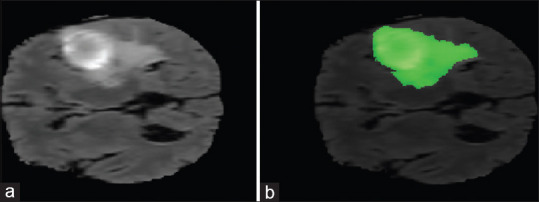

Background: Magnetic resonance (MR) image is one of the most important diagnostic tools for brain tumor detection. Segmentation of glioma tumor region in brain MR images is challenging in medical image processing problems. Precise and reliable segmentation algorithms can be significantly helpful in the diagnosis and treatment planning.

Methods: In this article, a novel brain tumor segmentation method is introduced as a postsegmentation module, which uses the primary segmentation method's output as input and makes the segmentation performance values better. This approach is a combination of fuzzy logic and cellular automata (CA).

Results: The BraTS online dataset has been used for implementing the proposed method. In the first step, the intensity of each pixel is fed to a fuzzy system to label each pixel, and at the second step, the label of each pixel is fed to a fuzzy CA to make the performance of segmentation better. This step repeated while the performance saturated. The accuracy of the first step was 85.8%, but the accuracy of segmentation after using fuzzy CA was obtained to 99.8%.

Conclusion: The practical results have shown that our proposed method could improve the brain tumor segmentation in MR images significantly in comparison with other approaches.